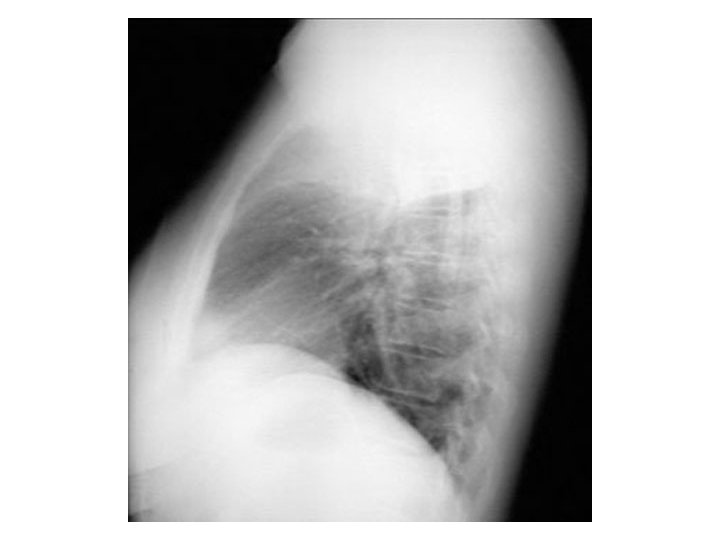

Extrapleural sign

Peripheral Sharp inner Indistinct outer Concave angles Extrapleural sign